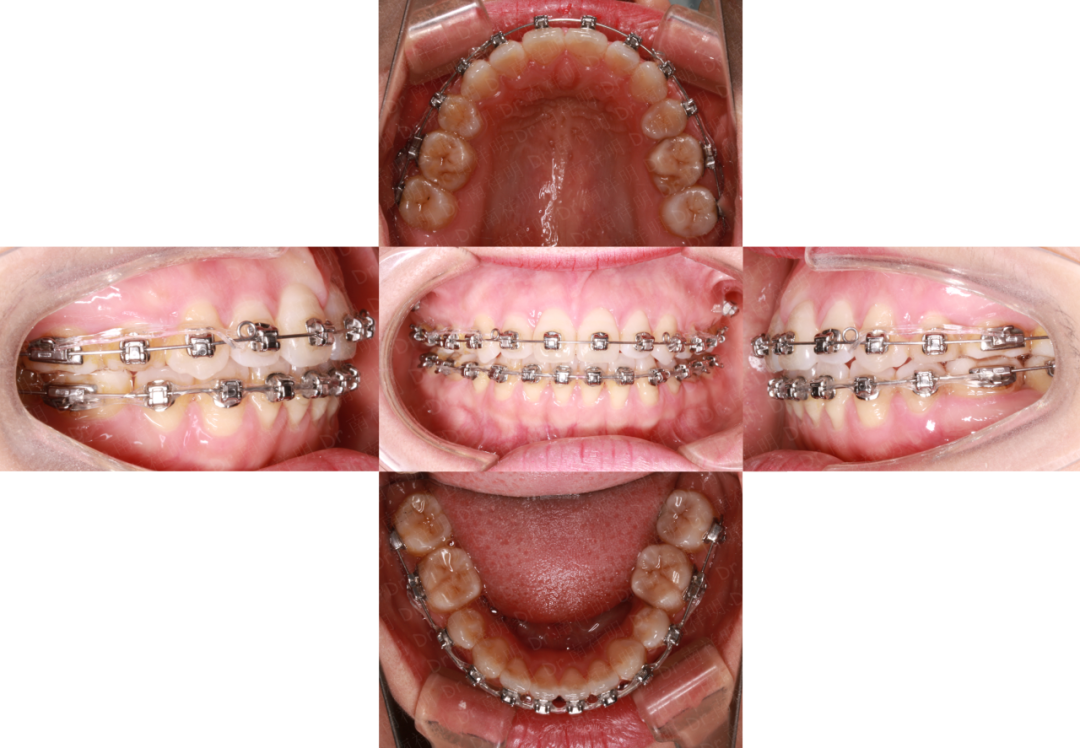

口内检查

磨牙关系:左侧远中关系、右侧远中关系

尖牙关系:左侧远中关系、右侧远中关系

覆合覆盖:上下前牙开合

speed曲线:呈反曲线

牙列:上牙列轻度拥挤,下牙列中度拥挤

中线:下中线左偏约1mm

动态检查:吞咽时伸舌,发音吐词不清

2016.1

治疗过程

拔除14.24.35.45.28

上颌戴改良TPA

下颌粘Damon Q 高转矩托槽

0.014NITI丝

31.41暂不粘接托槽

同期开始唇舌肌肉训练

为了避免上前牙因为排齐过程中过多的下垂,早期先不粘托槽